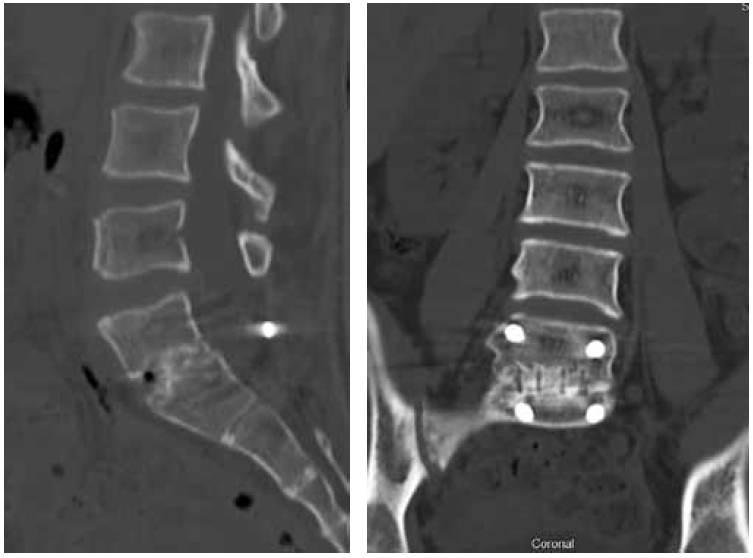

Considering the persistent pain syndrome after the conservative treatment and progressive nature of spondylolisthesis of L5, the following surgical intervention was performed: L5 laminectomy, microsurgical decompression of the spinal cord roots, complete reduction of the L5 vertebra, transpedicular fixation of the L5–S1 with additional fixation in the pelvic bone, and posterior interbody fusion of L5–S1. The duration of the surgery was 355 mins; the volume of blood lost was 800 ml. The patient was activated on the day 2 after surgery. During the postoperative period, the radicular pain syndrome had regressed completely, and no neurological disorders were detected. According to the control radiography, the restoration of the anatomical relationship of the vertebrae was noted. The position of the screws and implants was correct (Fig. 2). During the follow-up period, the patient had no complaints. After 1.5 years, MSCT revealed the formation of a reliable artifactual block, and the integrity of the surgical hardware was preserved (Fig. 3).

Fig. 3. MSCT of the lumbar spine 1.5 years after the surgery